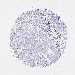

OVARIAN CANCER - Protein expressioni

A mouse-over function shows sample information and annotation data. Click on an image to view it in a full screen mode. Samples can be filtered based on level of antibody staining by selecting one or several of the following categories: high, medium, low and not detected. The assay and annotation is described here.

Note that samples used for immunohistochemistry by the Human Protein Atlas do not correspond to samples in the TCGA dataset.

Antibody stainingi

Antibody staining in the annotated cell types in the current human tissue is reported as not detected, low, medium, or high, based on conventional immunohistochemistry profiling in selected tissues. This score is based on the combination of the staining intensity and fraction of stained cells.

Each image is clickable and will lead to virtual microscopy that enables deeper exploration of all samples and also displays staining intensity scores, fraction scores and subcellular localization as well as patient and tissue information for each sample.

Antibody HPA051282

Carcinoma, endometroid